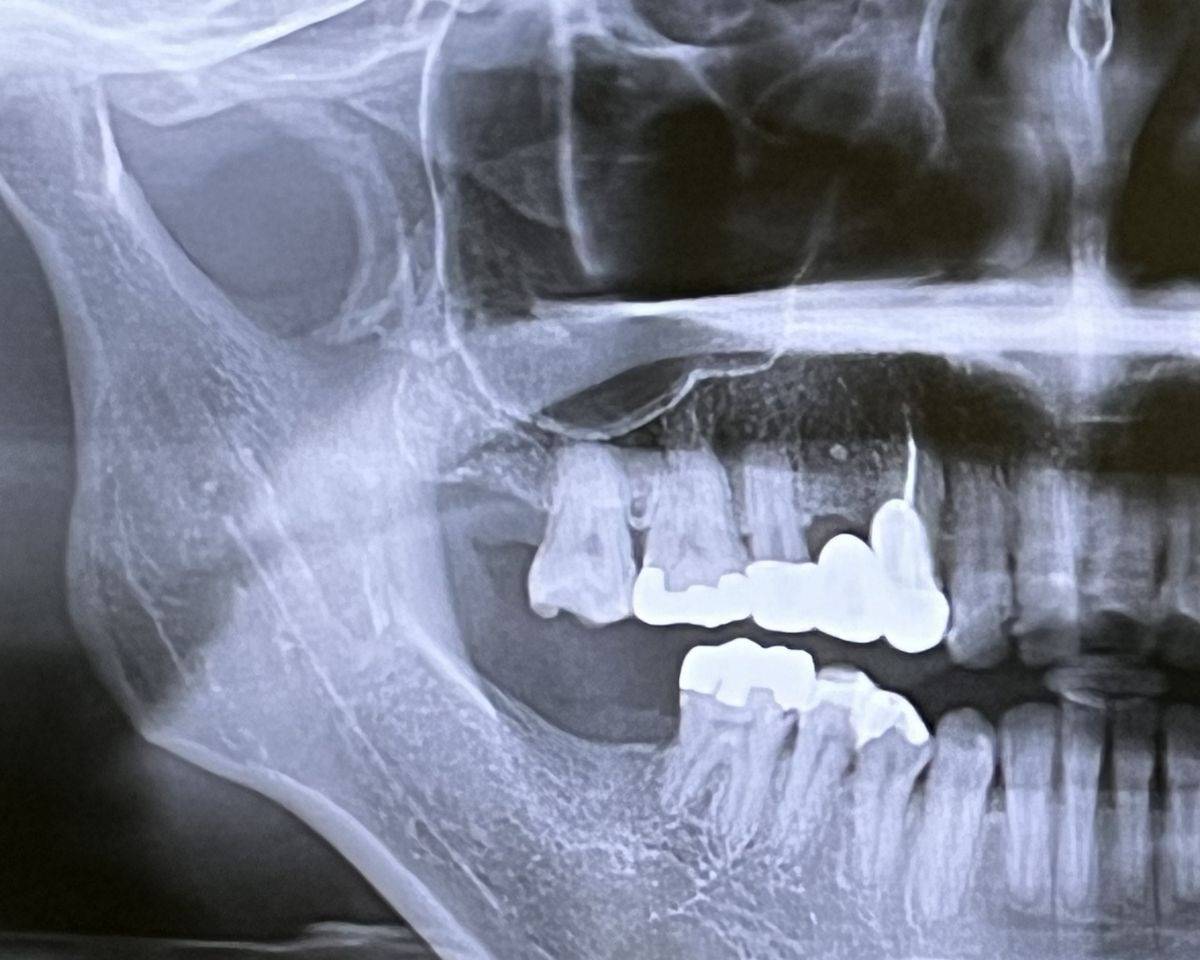

入れ歯に使用される素材もレントゲンの見え方に影響します。例えば、金属床の義歯では金属部分がレントゲン画像に白く強く写るため、その下に隠れた部分の骨の状態や病変が見えにくくなることがあります。これにより、診断の正確性が低下することがあります。そのため、素材選びの段階でも、診断に支障が出ないような設計上の配慮が必要です。

A.入れ歯に金属が含まれている場合、レントゲン写真に白い影が映り込み、骨の診断や虫歯、歯周病の有無、歯根の状態などが不明瞭になることがあります。特に顎の診断やかみ合わせを評価する撮影では、金属による画像の乱れが診断精度に影響を与えるため、検査前に撮影内容と入れ歯の素材を必ず確認することが必要です。